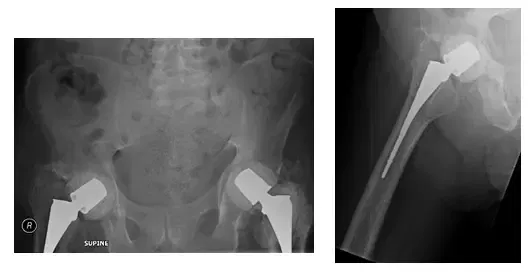

X-Ray shows pelvis post bilateral hip cement placer placement. X-Rays show cement spacers

X-Rays show bilateral hip spacer with no loosening or pelvic fractures